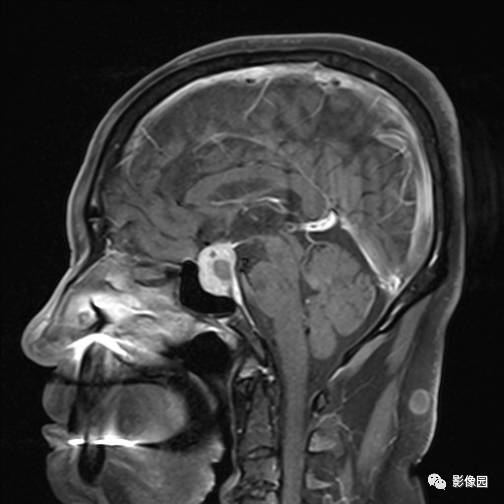

独孤求败:诊断为垂体瘤,蝶鞍扩大,鞍底下陷,鞍内见突向鞍上生长的团块状异常信号,T1WI呈等及稍高信号,T2WI呈等及低信号,增强扫描病灶呈明显不均匀强化;垂体柄显示不清,视交叉受压上抬。

lovethemoon:这不是颅咽管瘤,而是垂体瘤,颅咽管瘤时可见正常的垂体结构,此患者看不到正常的垂体结构,病变内短T1短T2异常信号是出血,垂体瘤合并了出血,颅咽管瘤囊变时的信号一般是长T1长T2。

【答案】垂体瘤合并出血